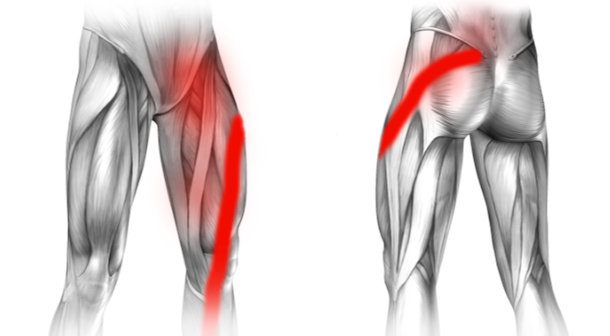

Lewostronna rwa udowa lub rwa kulszowa

Typową przyczyną zarówno rwy udowej jak i kulszowej jest dyskopatia lędźwiowa i ucisk na nerw rdzeniowy w kręgosłupie. Ucisk ten powoduje ból pośladka lub/i ból kręgosłupa lędźwiowego, który promieniuje do uda, podudzia i stopy. Ból w lewej pachwinie promieniujący do nogi jest bardziej charakterystyczny dla rwy udowej, jednak rwa kulszowa może również powodować dolegliwości w pachwinie.

W postawieniu prawidłowej i precyzyjnej diagnozy bardzo pomaga rezonans magnetyczny kręgosłupa lędźwiowego. To badanie bardzo dokładnie pokazuje odcinek lędźwiowy oraz uwidacznia ucisk na korzeń nerwowy wywołany przez przepuklinę kręgosłupa.

Leczenie rwy zależy od jej ciężkości. W łagodniejszych przypadkach wystarczą odpowiednie leki i fizjoterapia, natomiast w cięższych przypadkach pomagają zastrzyki nadtwardówkowe podawane precyzyjnie do miejsca ucisku nerwu w kręgosłupie. Operacje wykonuje się w najcięższych i opornych na mniej inwazyjne leczenie przypadkach.